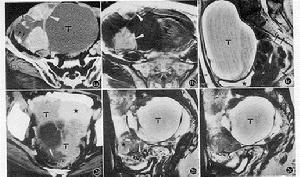

症狀卵巢類癌的大體觀是畸胎瘤中具有黃色實性結節,直徑3~15cm,平均9cm。鏡下瘤細胞大小一致,來自中腸的類癌細胞排列成島狀或巢狀;來自前腸和後腸的類癌癌細胞排列成小樑或花帶狀。電鏡下島狀類癌癌細胞的神經分泌顆粒不規則成啞鈴狀,而小樑花帶狀類癌的神經分泌顆粒為圓形或卵圓形

表現原發性卵巢類癌綜合徵90%以上發病時局限於一側卵巢一般不轉移。卵巢受累的範圍平均8cm,其中實性類癌成分占腫瘤體積的5%~95%